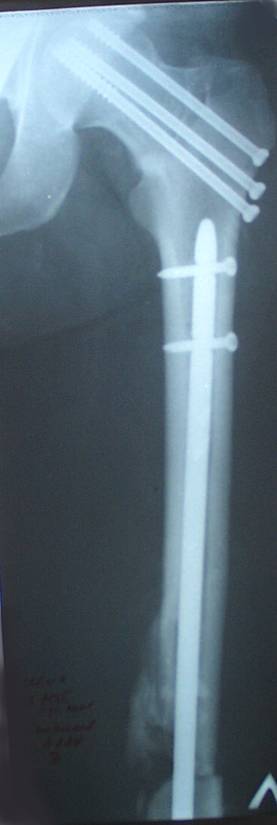

Уважаемый Сергей, избрав вариант DHS плюс ретроградный гвоздь Вы явно обезопасите себя от проблем, связанных с введением штифта через trochanteric fossa. Очень это может быть проблематично, Вы правы. Поэтому DHS плюс ретроградный гвоздь - спокойно выполнимый вариант, особенно в "чужом" отделении. Схожий свой случай из далёкого теперь уже 1999г. прилагаю, только вместо канюлированных винтов у Вас будет DHS (VHS). А если антеградный гвоздь - то только из тех, что предназначены к введению через верхушку вертела. И это тоже выполнимо, но сложнее. Мне так кажется.

Уважаемый Сергей Витальевич! Мы в похожем случае выбрали вариант DHS + DFN. Правда из 4 кортикальных винтов накладки DHS - 2 пришлось вводить монокортикально - уперлись в штифт.. На конечный результат это не повлияло. Ссылка здесь.